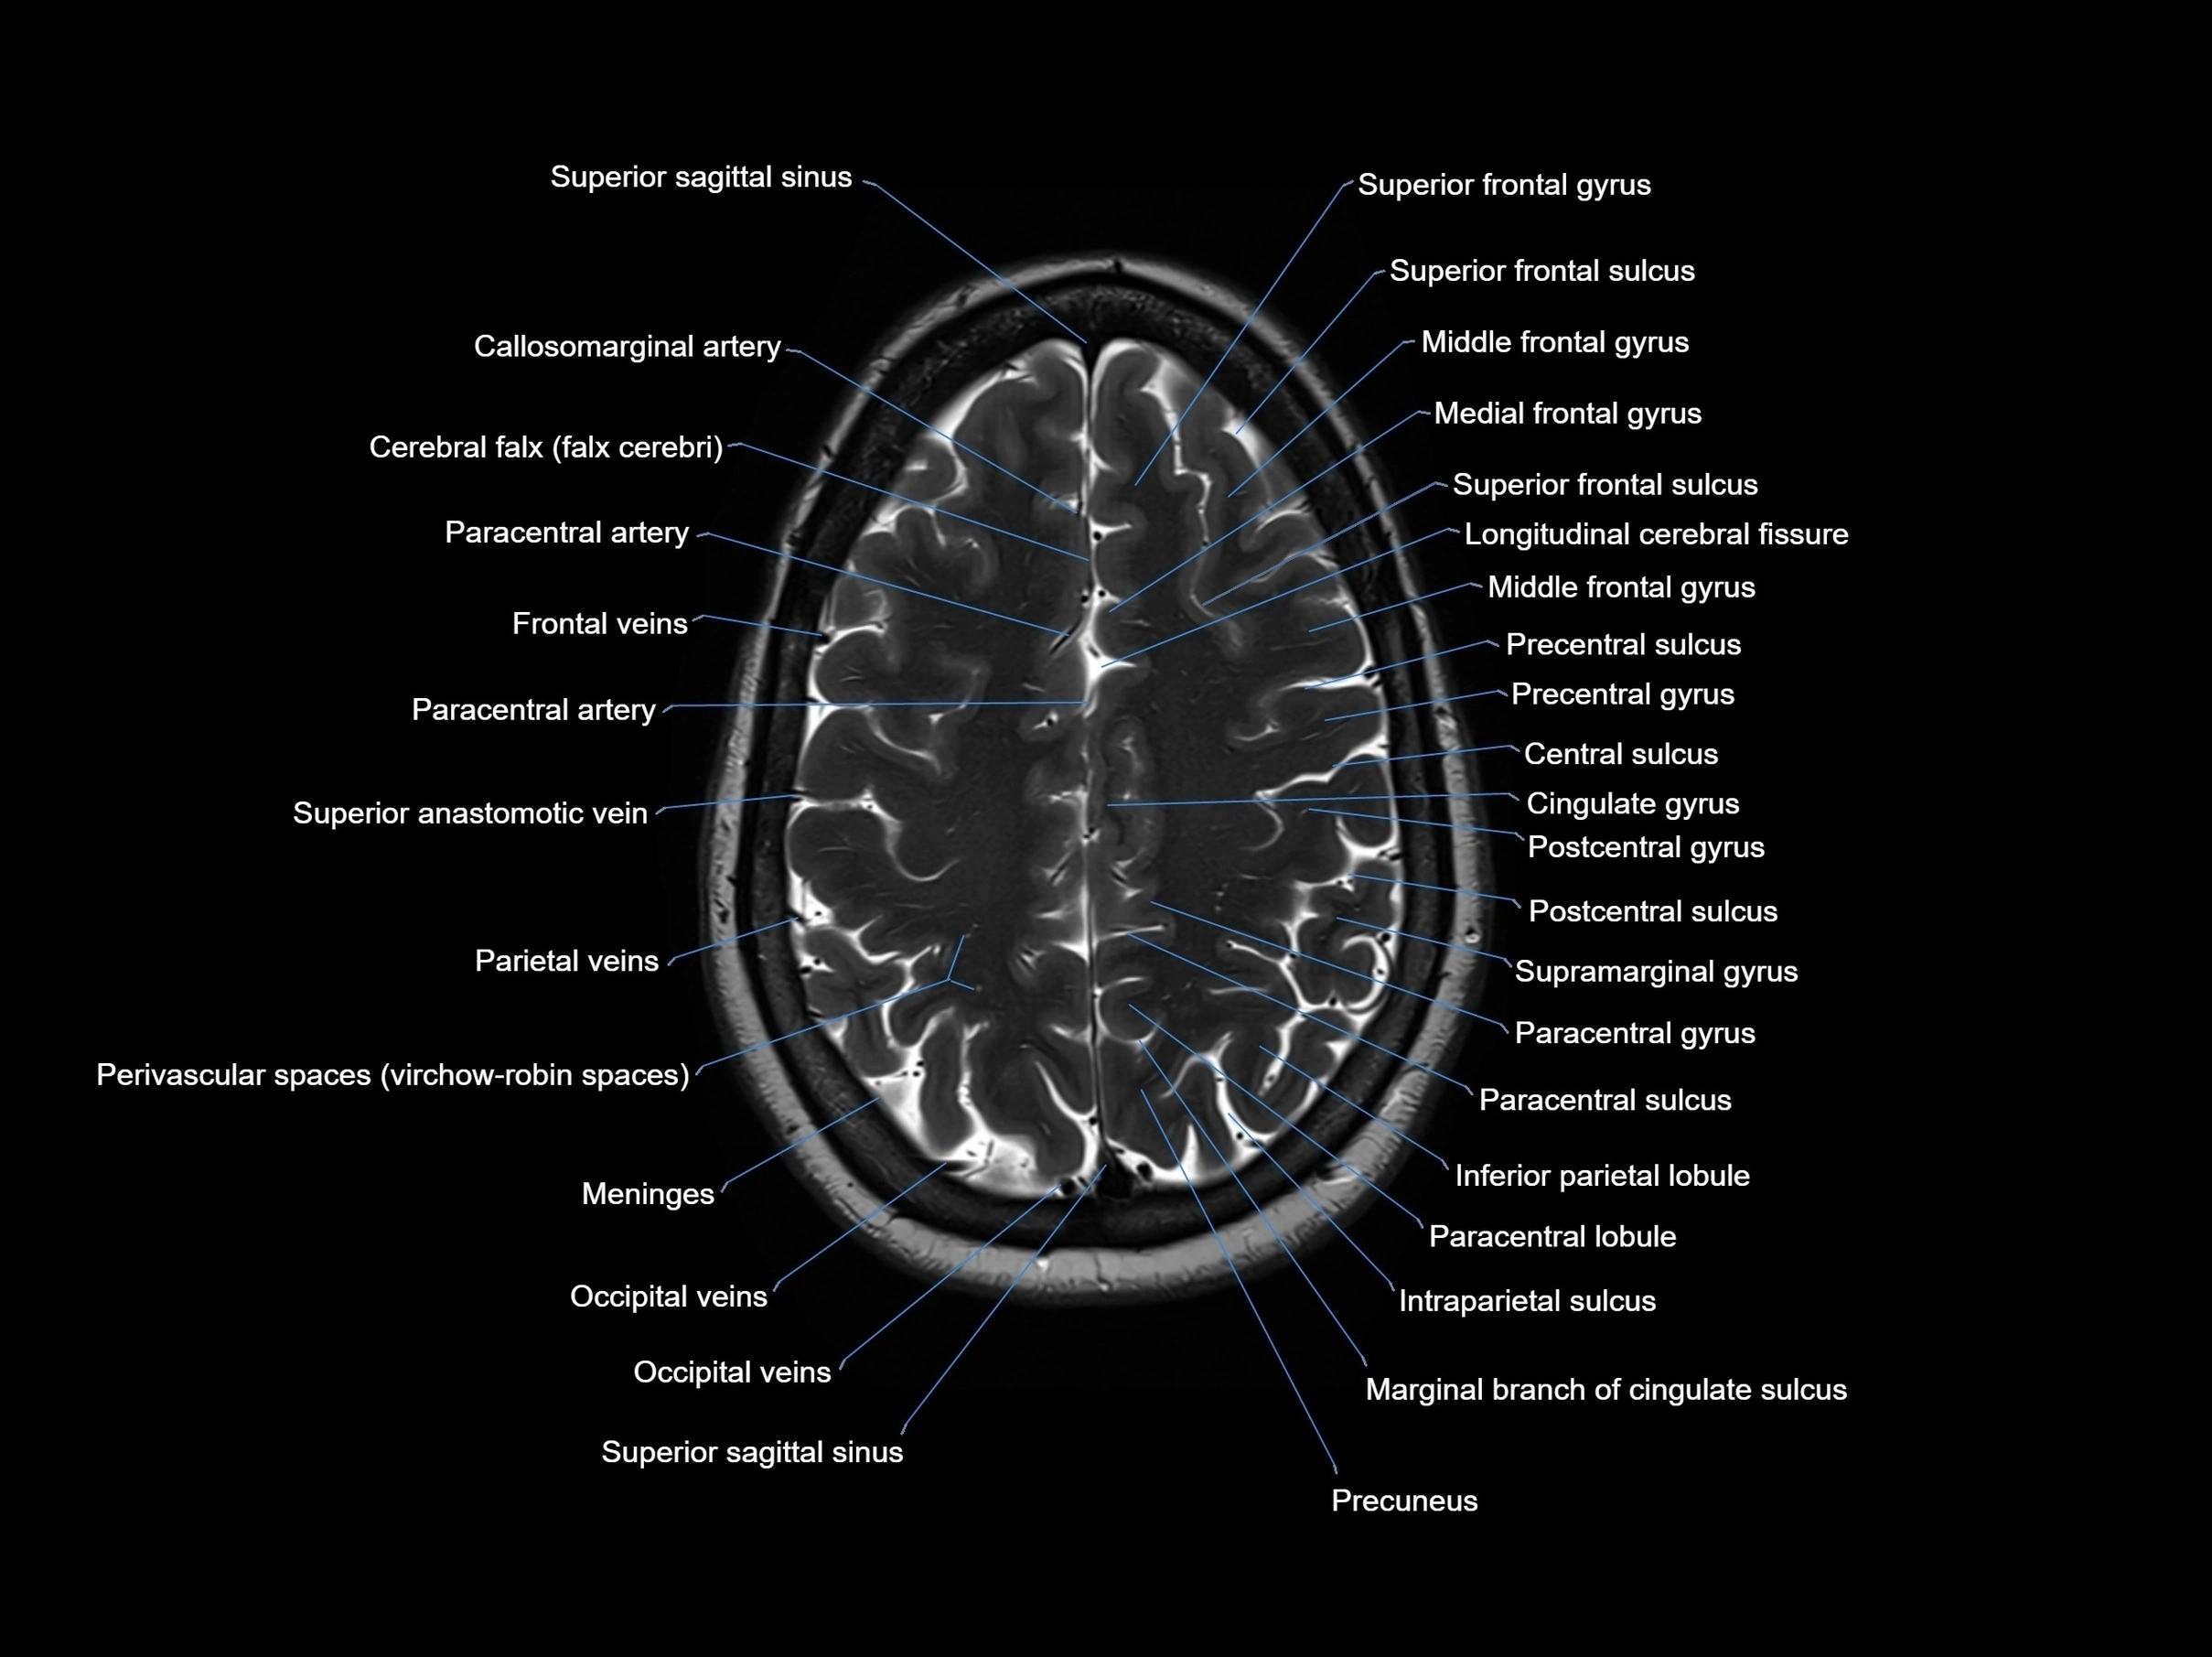

MRI images